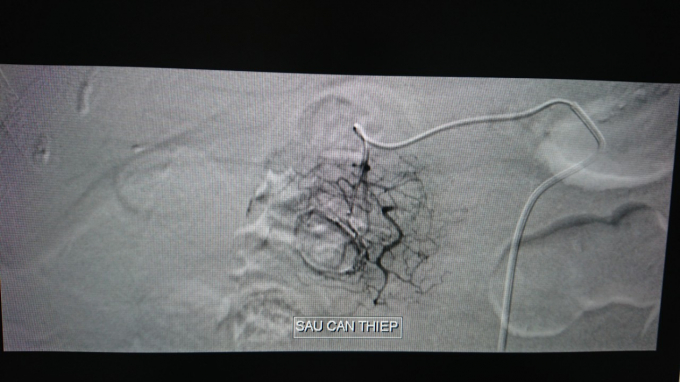

BS.CK1 Trần Công Khánh - Phó Khoa Chẩn đoán hình ảnh Bệnh viện tiến hành chụp phát hiện hình ảnh thoát mạch xuất phát từ động mạch vị tá tràng nghĩ xuất huyết từ tá tràng nên đã Luồn catheter vào động mạch gan chung để tìm điểm thoát mạch ở động mạch vị tá và đã thấy được điểm thoát mạch ở động mạch vị -tá , tiến hành tắc bằng keo Histoacryl và Lipiodol. Chụp kiểm tra không thấy thoát mạch. Thời gian thực hiện thủ thuật là 45 phút. Sau can thiệp bệnh nhân ổn định.

Sau can thiệp không còn thoát mạch